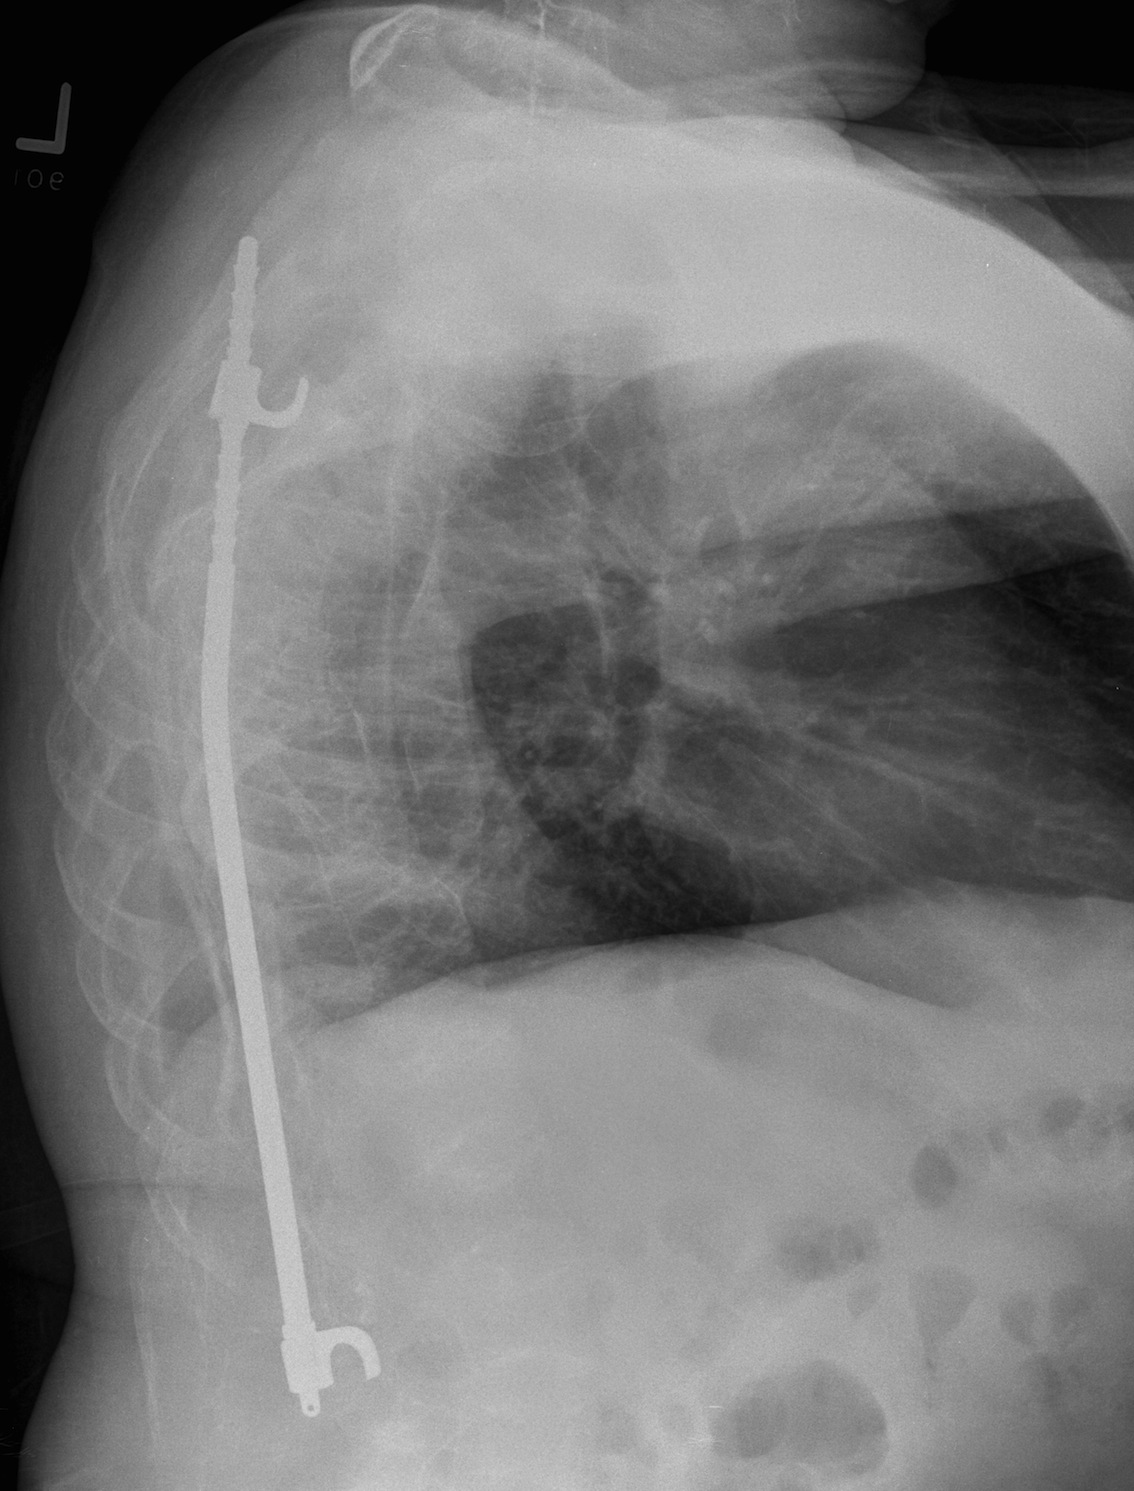

Posterior segmental instrumentation / arthrodesis

Augmentation with segmental sublaminar wiring

- to improve purchase in the osteoporotic bone